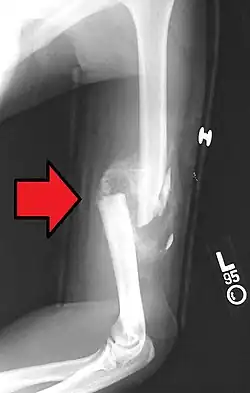

Distal humerus fractures usually occur as a result of physical trauma to the elbow region. If the elbow is bent during the trauma, then the olecranon is driven upward, producing a T- or Y-shaped fracture or displacing one of the condyles.[7]

Definitive diagnosis of humerus fractures is typically made through radiographic imaging. For proximal fractures, X-rays can be taken from a scapular anteroposterior (AP) view, which takes an image of the front of the shoulder region from an angle, a scapular Y view, which takes an image of the back of the shoulder region from an angle, and an axillar lateral view, which has the patient lie on his or her back, lift the bottom half of the arm up to the side, and have an image taken of the axilla region underneath the shoulder.[9] Fractures of the humerus shaft are usually correctly identified with radiographic images taken from the AP and lateral viewpoints.[12] Damage to the radial nerve from a shaft fracture can be identified by an inability to bend the hand backwards or by decreased sensation in the back of the hand.[5] Images of the distal region are often of poor quality due to the patient being unable to extend the elbow because of pain. If a severe distal fracture is suspected, then a computed tomography (CT) scan can provide greater detail of the fracture. Nondisplaced distal fractures may not be directly visible; they may only be visible due to fat being displaced because of internal bleeding in the elbow.[7]